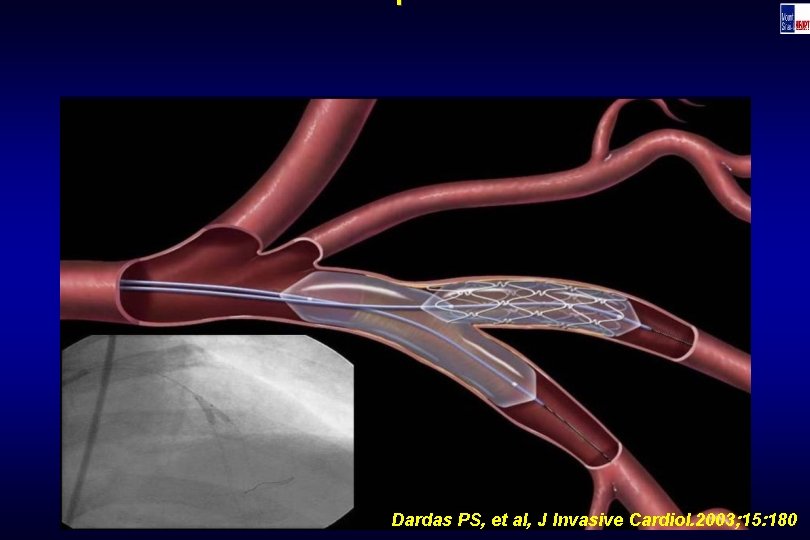

Technique Dardas PS, et al, J Invasive Cardiol. 2003; 15: 180

Technique Dardas PS, et al, J Invasive Cardiol. 2003; 15: 180

Technique Dardas PS, et al, J Invasive Cardiol. 2003; 15: 180

Technique Dardas PS, et al, J Invasive Cardiol. 2003; 15: 180

Technique Dardas PS, et al, J Invasive Cardiol. 2003; 15: 180

Technique Dardas PS, et al, J Invasive Cardiol. 2003; 15: 180